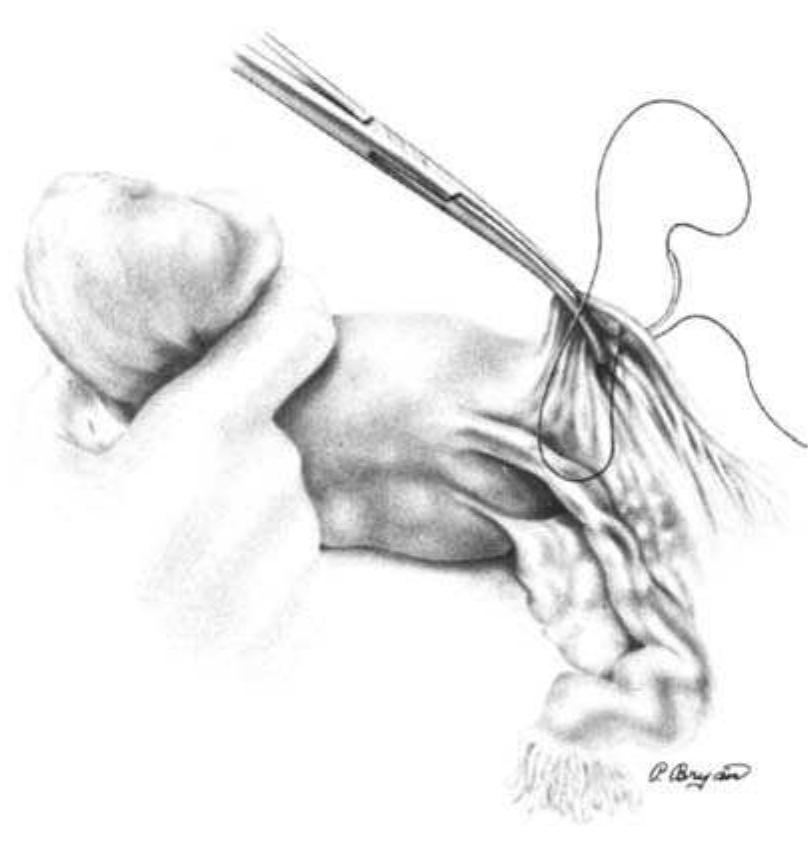

Background: Total scalp avulsion is a rare and devastating event. Microsurgical replantation is the sole method to achieve an ideal cosmetic outcome. In the literature, most studies have reviewed limited sample sizes. Most authors report better outcomes when a greater number of microvascular anastomoses are used. This strategy remains controversial, as some authors have suggested that one artery may be sufficient. Methods: From 2005 to 2008, seven patients who sustained scalp avulsion underwent microsurgical replantation. All of the vascular anastomoses were made with a branch of the superficial temporal artery. We did not use vein grafts. The ischaemia time was 4e16 h. Results: In six cases, a single artery and one to two veins were anastomosed; in another case, two arteries and three veins were anastomosed. Six of the seven scalp replantations were successful and achieved normal hair regrowth. In five of the six successful cases, we performed a single-artery anastomosis. Conclusion: Scalp avulsion is rare around the world but occurs relatively frequently in our country due to the lack of safe and secure working conditions in agriculture and industry. In cases where multiple arterial anastomoses are not possible, the present findings suggest that one branch of the superficial temporal artery may be sufficient to reperfuse the replanted scalp and achieve excellent aesthetic results.

The freafmenf of choice for the avulsed scalp is microvascular replanfafion. Affer replanfafion there are numerous arterial anasfomoses, with venous congestion. UstMlly an effort to establish it&w through fwo arferial anasfomoses is made. We elected to anasfotnose one artery and mulfipk veins in each of our pafienfs. We present three consecufive successful replanfafions of total scalp au&on, using only one arterial anasfomosis, and mulfiple veins. Surprisingly, fwo of the patients regained their abilify to elevate fheir eyebrows actively.

Microsurgery, 1993

A successful replantation of a totally avulsed scalp. including both eyebrows, with only one arterial and one venous anastomosis to the superficial temporal vessels is described. Apart from a small partial skin necrosis of the right eyebrow, the entire transplant survived. Subsequently, the patient required only minor additional skin grafting, correction of scars hair micrografts. Replantation of the total scalp based on two or more vessels has previously been recommended and reported elsewhere. In the present case, complete survival of the scalp on only one artery and one vein was demonstrated, indicating that replantation should be considered even if available vessels for anastomosis are minimal. 8 1993 Wiley-uss. Inc. with a skin expander, and reconstruction of the eyebrow with MCROSUROERY 1 4-1SS3 Es wird die erfolgreiche Replantation cines komplett ausgerissenen Skalps einschlieSlich beider Augenbrauen iiber eine Anastomosierung der A. und V. superficialis temporalis vorgestellt. AuOer einer kleinen Teibkrose der Haut im Bereich der rechten Augenbraue blieb das gcaamte Transplantat vital. Im weiteren Verlauf m t i g t e die Patientin lediglich geringfiigige ZuSiItzliche Hauaransplante, eine Narbenkorrektur mittels Hautexpander und die Rekonstruktion einer Augenbraue mit Minihaamansp lantaten. Die Replantation des gesamten Skalps iiber zwei oder meh GeFaSe wurde bereits friiher empfohlen und auch an anderer Stelle berichtet. Im vorliegenden Fall wurde gezeigt, das der Skalp in toto vital blieb bei nur einer Anastomose einer einzigen Arterie und einer einzigen vene. somit konnte ndchgewiesen werden, das eine Replantation unbedingt ins Auge gefaRt werden SOU, selbst wenn nur spiirliche Gefiiiiverhiiltnisse zur Anastomosierung vorhanden sind.

European Journal of Plastic Surgery, 1997

The authors report their experience in successful reimplantation of avulsed scalp in two patients with one arterial and one venous anastomosis to the superficial temporal vessels. In both cases a double vein graft, harvested from the dorsum of the hand, was interposed between the pedicle of the scalp and the recipient temporal vessels to avoid tension after trimming of the damaged segments. Scalp replantation based on two or more vessels has previously been reported in the literature. In the present cases, the complete survival of the scalp on only a single vascular pedicle suggests that replantation should be considered also when the available vessels for the anastomosis are few. Moreover, even if these reconstructions are lengthy, a prolonged ischemic interval does not appear to be a significantly limiting factor for the success of the revascularization. The cosmetic and psychological success of these cases lend support to the idea that one should always attempt a microvascular replantation of avulsed scalps.

Background: Soft tissue defects of the scalp may result from multiple etiologies and can be challenging to reconstruct. We discuss our experience with scalp replantation and secondary microvascular reconstruction over 36 years, including techniques pioneered at our institution with twin-twin scalp allotransplant and innervated partial superior latissimus dorsi (LD) for scalp/frontalis loss. Methods: A retrospective review of all patients presenting with scalp loss requiring microvascular reconstruction at a single center was performed from January 1971 to January 2007. Medical records were reviewed for age, gender, defect size/location, etiology, type of reconstruction, recipient vessels used, vein grafts, and complications. Results: Thirty-three patients were identified; mean age was 33 years (range, 7-79). Mean scalp defect size was 442 cm 2 (range, 120-900 cm 2). Thirty-six microvascular reconstructions were performed; of these, 10 scalp replants and 26 microvascular tissue transfers. Of these 26, 17 were LD based (partial superior LD with and without reinnervation, LD combined with serratus, LD combined with parascapular, LD combined with split rib, LD only) and 2 free scalp allotransplant among others. The superficial temporal artery and vein was used as recipient vessels in 70% of cases. Overall, microvascular success rate was 92%; complications occurred in 14 cases, nine major (tumor recurrence [n 5 2], partial flap loss [n 5 2], replant loss [n 5 3, size <300 cm 2 ], hematoma [n 5 2]) and five minor (donor site seroma /hematoma [n 5 3], flap congestion [n 5 1], superficial wound infection [n 5 1]). Conclusions: Every attempt should be made at scalp replantation when the patient is stable and the parts salvageable. Larger avulsion defects had higher success rates after replantation than smaller defects (<300 cm 2), with the superficial temporal artery and vein most commonly used for recipient vessels (P 5 0.0083). Microvascular tissue transfer remains a mainstay of treatment for scalp defects, with LD-based flaps, demonstrating excellent versatility for a range of defects. V V